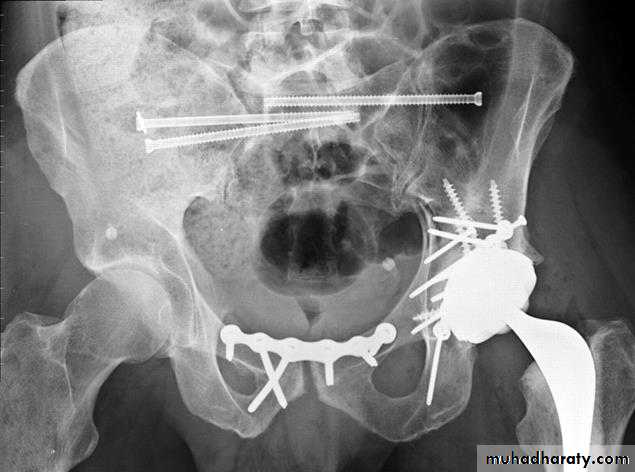

open reduction and internal fixationindications

total hip arthroplasty indications

usually elderly patients with pre-existing arthritis

post-traumatic arthritis in all ages